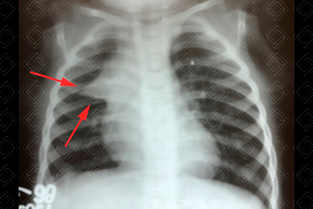

Texto alternativo para a imagem Figura 2. Créditos: Dra. Elazir Mota - Rio de Janeiro/RJ

• Sinal da incisura: Observa-se a junção do timo e da silhueta cardíaca na figura 2 .